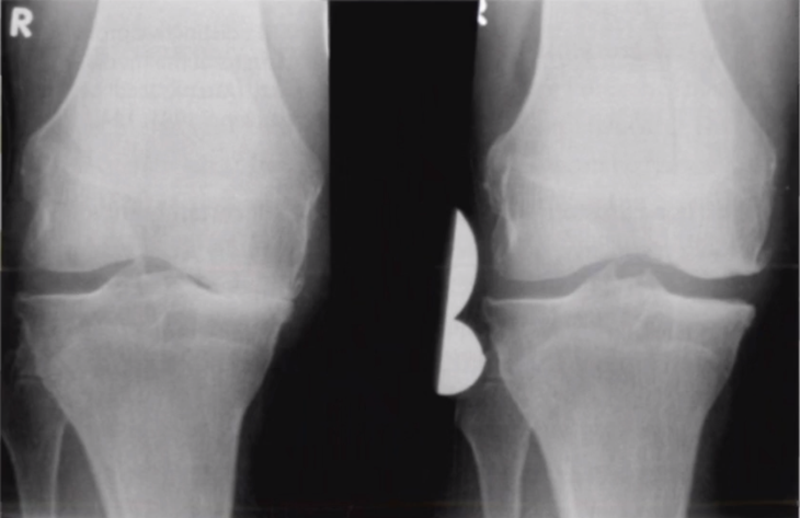

五、关于力线与假体位置——是否要求全长片?

牛津单髁课程表明,单髁只纠正关节内畸形,恢复下肢得病前的力线,不纠正关节外畸形。

但实际术后需要通过全长片来判断是否能取得好的力线,判断有无过度矫正或矫正不足的情况出现。还需要通过全长片区分内翻畸形的来源在哪里,是否能矫正,对适应证的选择有一定帮助。如果术后下肢整体力线外翻3°,则说明外侧间室压力明显升高。

小结:对于下肢整体力线,首先保证术后力线不能外翻,术后力线内翻不能超过10°,而术前关节外畸形不能超过10°。

除了下肢整体力线,还要考虑假体位置。理想状态下,假体位置对位好,力线轻度内翻。

但有时候力线好,假体和外侧关节线会成角,那么对于此种情况,应如何判断假体位置内外翻定义?和外侧关节线比较,属于外翻假体;和下肢机械轴比较,属于中立位假体。

小结:判断股骨胫骨假体位置,是基于局部X线的判断,是考虑行走时关节线的方向为基准,此时内外翻不能超过5°,而不能从全长片来判断。